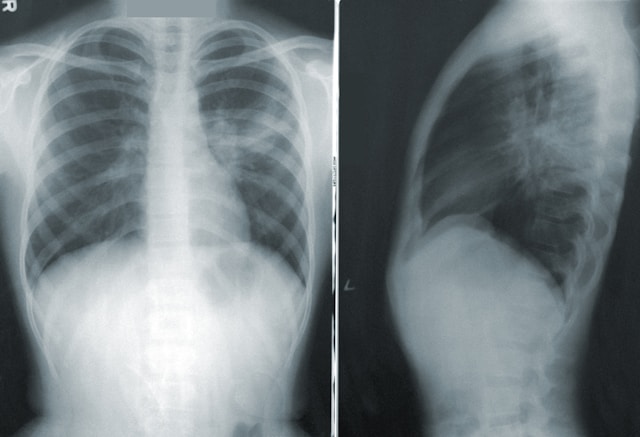

2. 폐암 치료와 관리 방법

폐암 치료에는 장기적인 폐 청소와 관찰 과정이 포함됩니다. 치료가 성공하면 5년 후 완치 판정을 받을 수 있습니다.

폐에는 먼지가 많이 쌓이는데, 이로 인해 치료가 어려워질 수 있습니다. 특히 끈끈한 가래가 기침으로 배출되지 않는 경우가 많습니다. 하지만 폐 청소용 물을 마시면 가래가 부드러워져 배출이 쉬워질 수 있습니다.